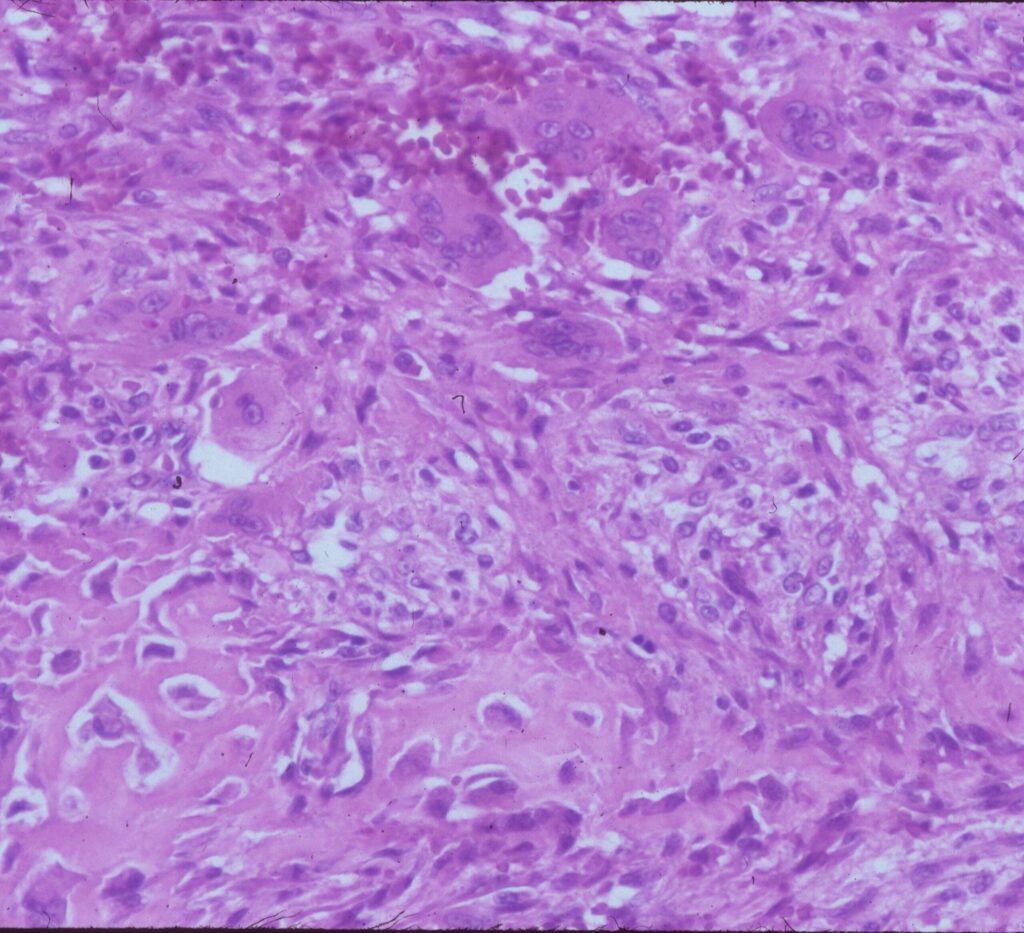

Microscopic Pathology

- Hemorrhagic tissue with large cavitary spaces divided by septum of spindle fibroblastic cells, inflammatory cells and few giant cells.

- Osteoid formation could be noted (reactive and benign in nature)

Fig 3 a,b,c. Microscopic pathology of an Aneurysmal Bone Cyst (ABC):

Fig 3c: High power view of an ABC: Demonstrates reactive bone formation within the wall of the cystic cavities. This is reactive bone and different from the lace like immature bone layed down by an osteosarcoma